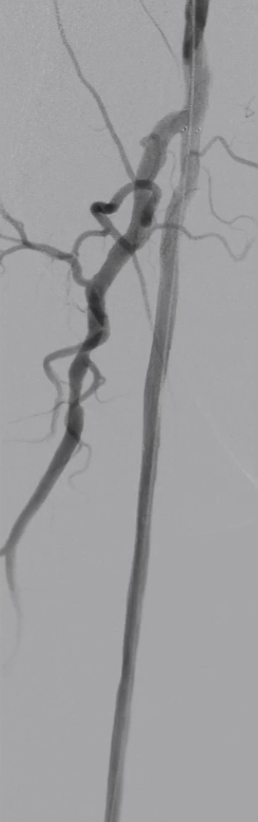

手术结果:

血流通畅,解剖与功能双重改善

最终造影显示:支架定位准确、形态良好,股浅动脉、腘动脉及膝下动脉显影清晰,血流通畅。

短期疗效

体格检查:右侧胫后动脉恢复正常搏动;

ABI:右侧从术前0.65提升至0.92,缺血症状显著改善。

远期随访(术后半年)

CTA复查:支架内血流通畅,无明显内膜增生,证实手术远期有效性。